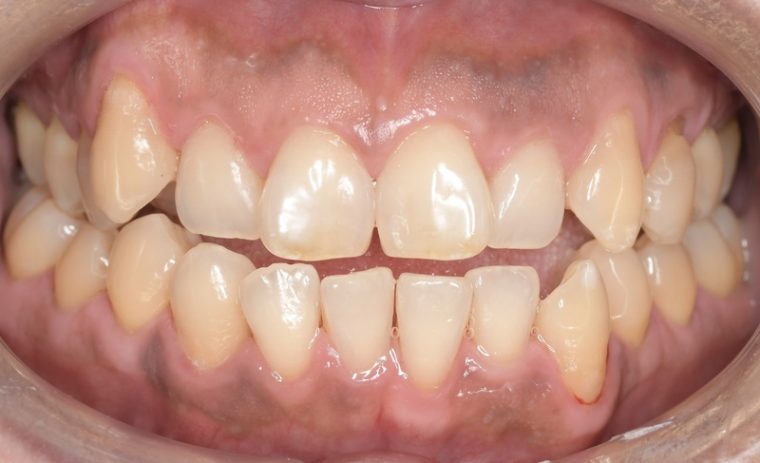

Before

After

| 年齢・性別 | 52歳・女性 |

|---|---|

| 主訴 | クリーニングしたい |

| 治療内容 | スケーリング・PMTC |

| 治療期間 | 60分 |

| 治療費 | 約7,000円 |

| リスク・副作用 | 知覚過敏、歯肉退縮 |

| 治療方針 | 歯石とステインを除去して、今後は定期検診でのクリーニングと併せてガムピーリングやホワイトニングを行います。 |

| 担当者所見 | 歯肉の色素沈着が目立つため、ガムピーリングを行いながらホワイトニングを行うことをおすすめします。 |